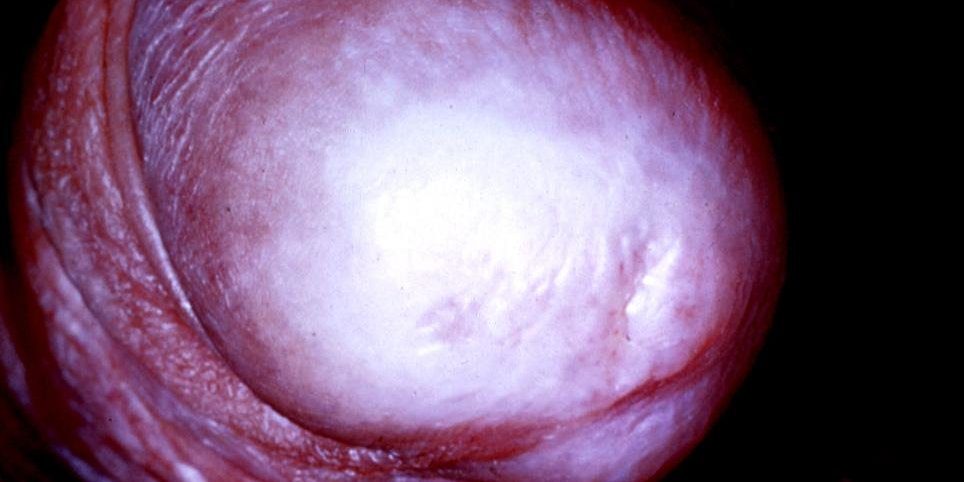

Balanitis Kserotika Obliterans (BKO) Nedir?

Balanitis Kserotika Obliterans (BKO) Nedir? Balanitis kserotika obliterans (BKO) ya da ...